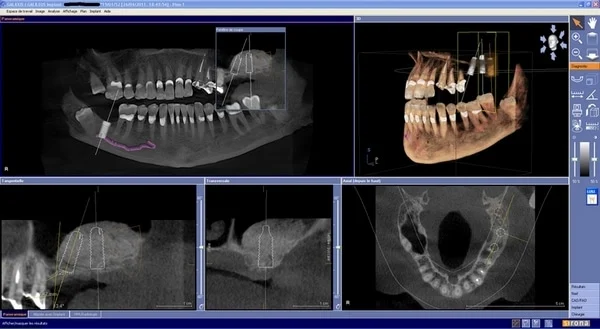

Le principe du **Cone Beam dentaire** repose sur l’acquisition de multiples images 2D à partir de différents angles autour de la tête du patient. Ces images sont ensuite reconstruites par un logiciel sophistiqué pour former un modèle 3D précis de l’anatomie buccale et maxillo-faciale. Contrairement aux scanners médicaux conventionnels, le **CBCT dentaire** est optimisé pour les tissus durs, offrant une haute résolution spatiale essentielle pour visualiser les détails les plus fins des structures osseuses et dentaires.

Résultats immédiats et analyse par le dentiste

L’un des avantages majeurs du **CBCT dentaire** est la disponibilité quasi immédiate des images après le scan. Une fois les données acquises, un logiciel spécialisé les reconstruit en un modèle 3D détaillé sur l’ordinateur. Le dentiste peut alors analyser ces images sous différents angles et coupes (axiales, coronales, sagittales, obliques), offrant une vue complète et sans superposition des structures dentaires et osseuses. Cette analyse rapide permet une discussion immédiate avec le patient concernant le diagnostic et les options de traitement.

Les structures visibles et analysables sont nombreuses : de la position exacte d’une dent de sagesse incluse à la détection de kystes inapparents en 2D, en passant par la cartographie des canaux pulpaires avant un traitement endodontique, l’état des sinus, l’intégration des bridges ou même la qualité osseuse pour une future pose d’implant dentaire. Cette transparence et cette rapidité dans le diagnostic renforcent la confiance du patient et facilitent une prise de décision éclairée.